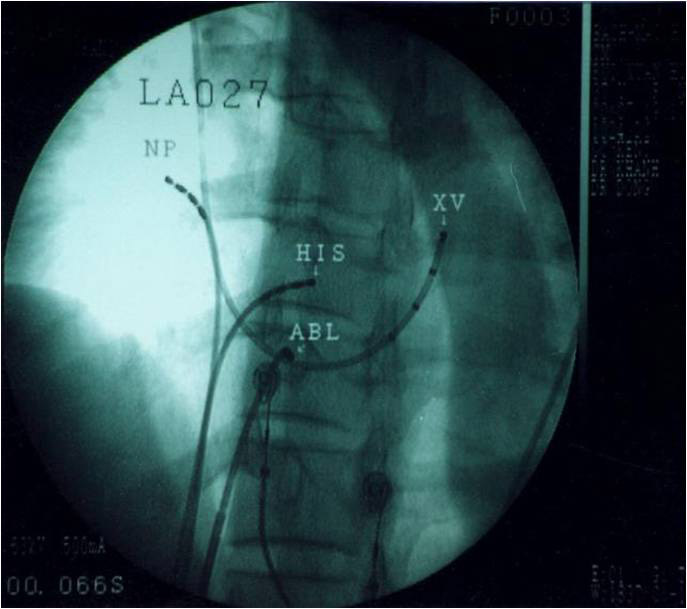

Hình 11: Vị trí các ống thông trên hình ảnh X quang trong triệt đốt đường chậm ở tư thế nghiêng trái 30 độ (trái) và nghiêng phải 30 độ (phải): NP: điện cực cùng cao nhĩ phải, His: điện cực vị trí bó His, XV: điện cực xoang vành, TP: điện cực mỏm thất phải, Abl: điện cực triệt đốt được đưa vào vùng đáy của tam giác Koch, dưới vị trí điện cực bó His khoảng 2 cm và ngang mức với lỗ xoang vành.